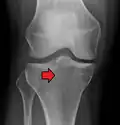

Subtle tibial plateau fracture on an AP X ray of the knee -

A tibial plateau fracture seen on X-ray